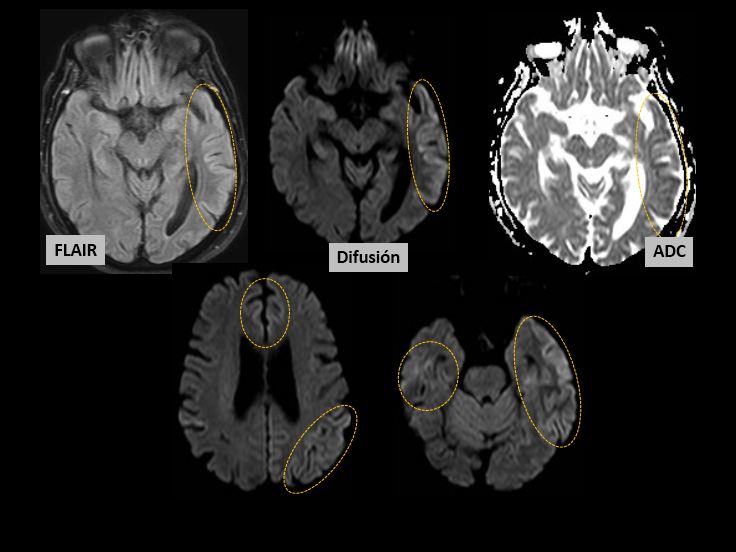

Figura2

Afectación de la corteza con patrón “giriforme”, énfasis en la difusión:

-Temporooccipital izquierda sobre todo

-Frontal parasagital bilateral, parietal izquierdo, temporobasal bilateral